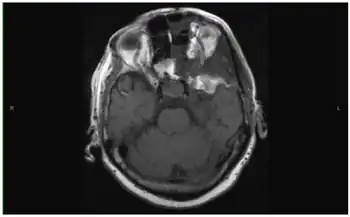

Brain tumor can be visualized very well on CT scan, but MRI gives better detail and is the preferred study. Clinical localization of brain tumors may be possible by virtue of specific neurologic deficits or symptom patterns. Tumor at the base of the frontal lobe produces inappropriate behavior, optic nerve atrophy on the side of the tumor, papilledema on the other side, and anosmia.